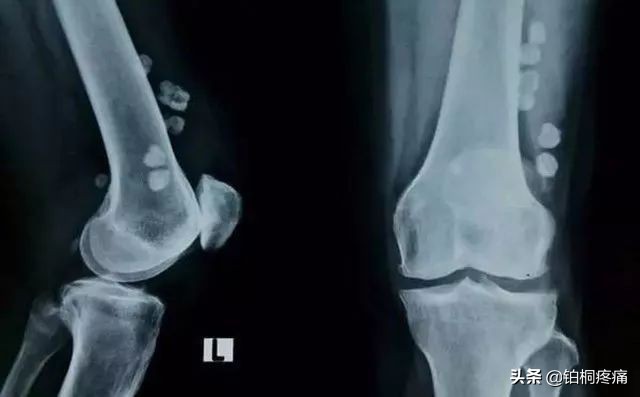

01、骨关节炎

中老年人常出现膝盖红肿痛、上下楼梯痛、坐起立行时膝部酸痛等不适,在休息后缓解。如果拍片子发现关节磨损、骨质增生、关节间隙变狭窄,甚至出现关节畸形,说明膝关节退化到了骨关节炎的阶段,已经不可逆转,需要引起重视。轻者可采取康复、止痛治疗,稍严重者可进行疼痛科专有微创介入治疗。

04、膝关节内游离体

走路时突然出现腿发软、关节卡住感,如卡在一个姿势不能动弹,这是因为关节软骨磨损脱落后形成游离体被卡在关节间隙中,轻轻抬腿并甩一甩,卡住的感觉可以消失。此外患者会因滑膜受到刺激而出现关节肿胀、积液等症状。游离体反复卡于软骨面之间,可导致软骨的继发性磨损。

关节内如果有游离体产生,不论大小,都建议尽快取出。否则膝关节的磨损越来越快、疼痛的症状会越来越重。